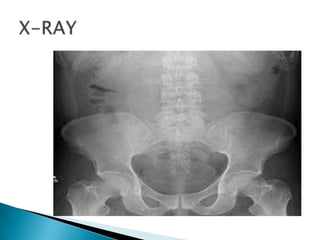

Acute abdominal x-ray series -Lack of free

air does not rule out perforation

Abdominal x-ray series-Air-fluid levels,

dilated loops of bowel,Lack of gas in distal

bowel and rectum